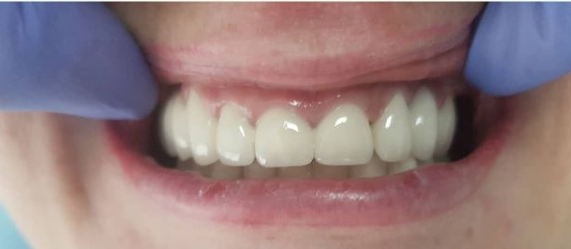

Стоматологическая клиника МИЛА ДЕНТ (MILA DENT)

Протезирование зубов